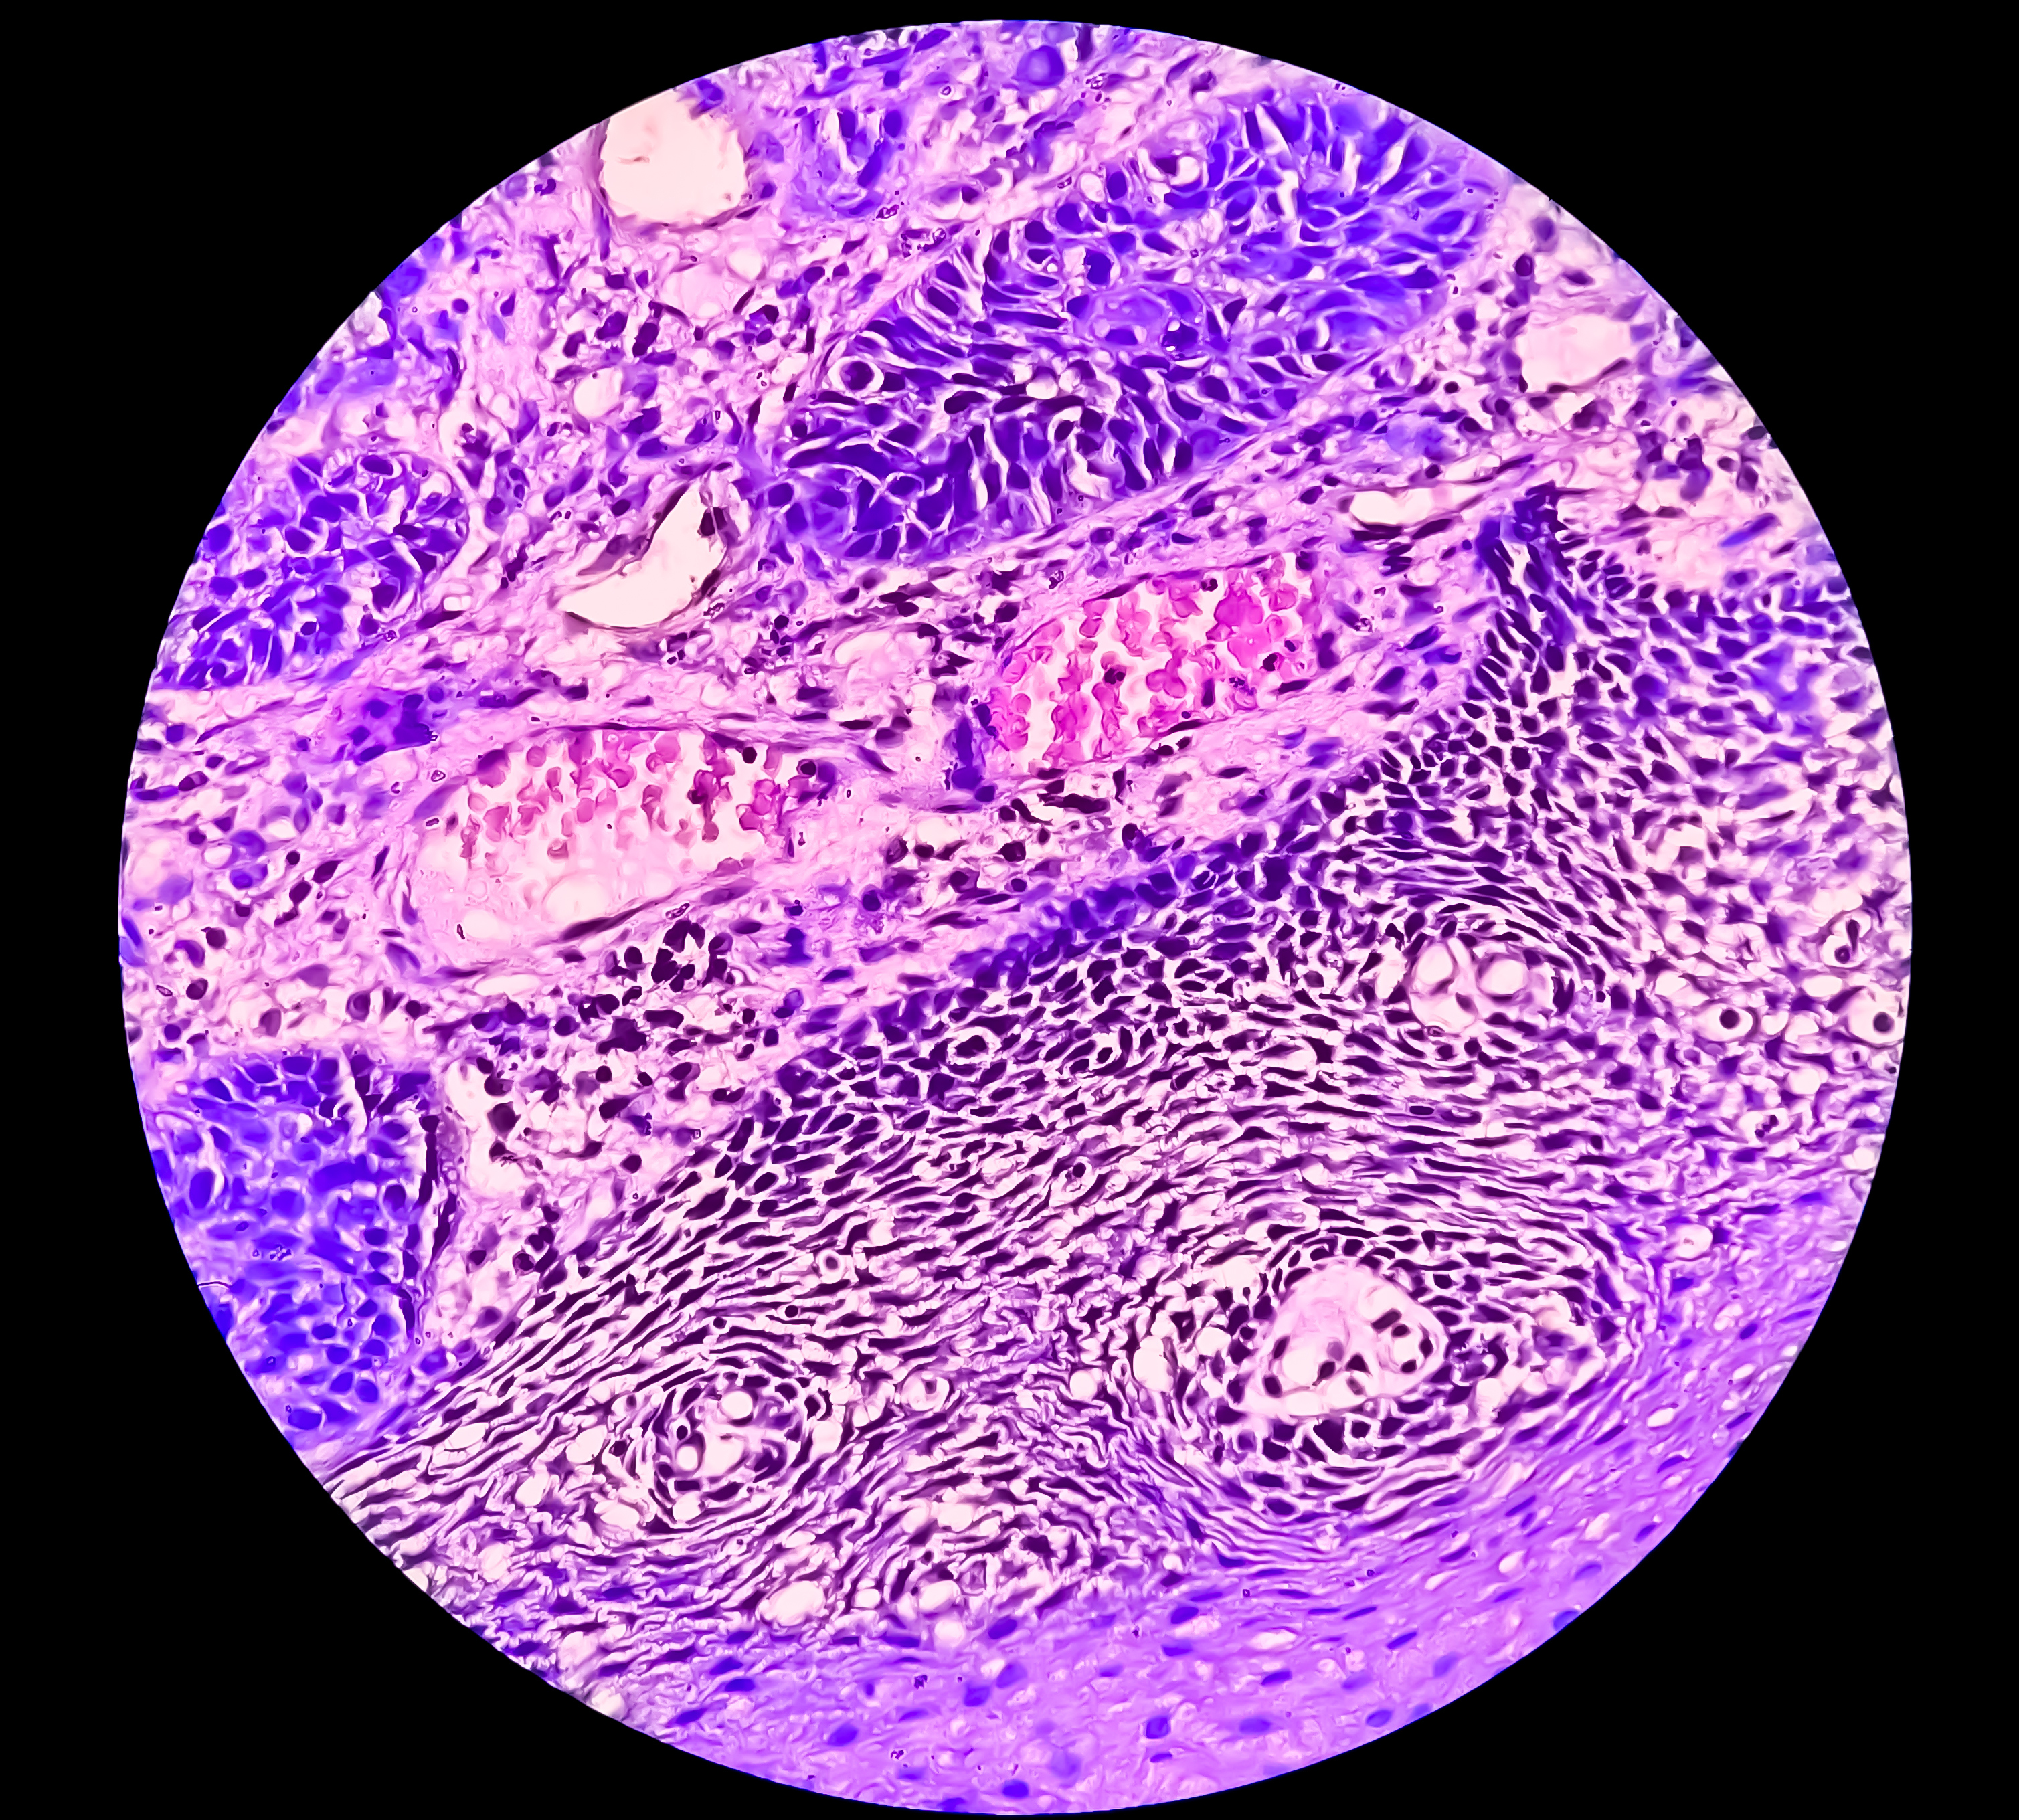

Merkel Cell Carcinoma (MCC) is an uncommon type of Skin Cancer that starts when Merkel cells grow out of control.

Merkel Cell Carcinoma often first appear as a single pink, red, or purple bump that is not usually painful. Sometimes the skin on the top of the tumour might break open and bleed. As it looks like many other types of skin cancers, diagnosis is usually only made after the tumour has been biopsied.